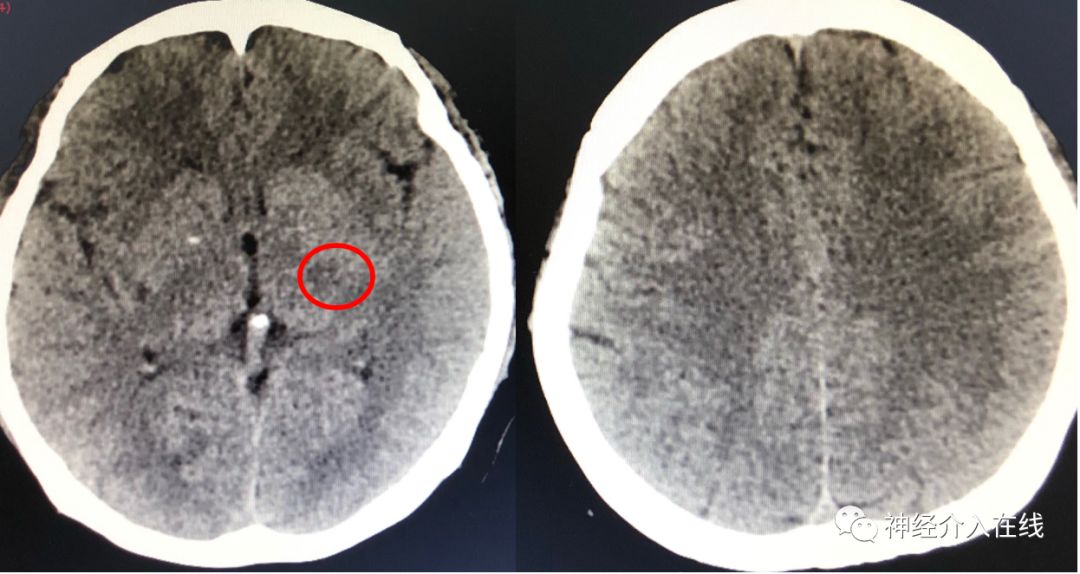

Case:46岁,女性,主因突发意识不清伴言语不能、右侧肢体活动不利30min,2017-7-20神经介入科院内绿色通道会诊患者。本例患者刷牙、洗漱过程中突发言语不能、右侧肢体活动不利。NIHSS:15分。患者3天前因“胸闷心悸2年”心外科行二尖瓣、主动脉瓣机械瓣置换术,术后服用华法令2天,每日监测INR:1.11。2019年既往高血压,糖尿病,风湿性心脏病,房颤病史。虽是院内绿色通道的患者,具有发病时间窗优势,但是患者心脏机械瓣膜置换术后无法完成头MRI检查,另外发病时至周末没有急诊CTA检查条件。因此,这个患者真真滴是凭借发病6h以内+NIHSS≥9分和一张CT(术前ASPECTS评分:9分)上台啦(患者3天前开胸手术——静脉溶栓禁忌),术前NIHSS:21分。